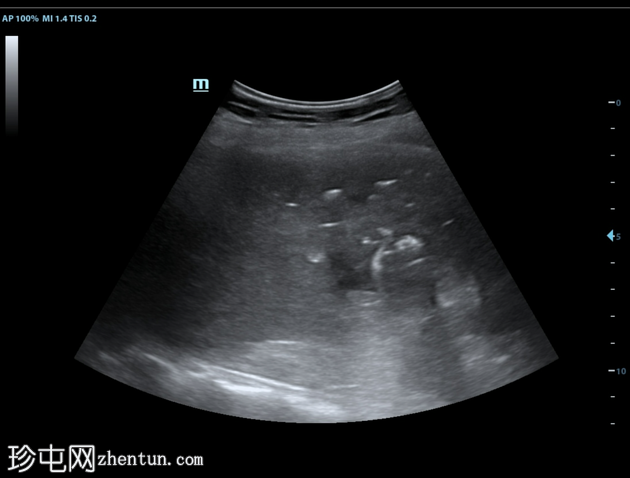

超声检查

2.png

肝脏第6和第7段可见多个高回声气体腔,遮挡肝脏后部

肝脏其他部位形态及回声纹理正常

胆总管扩张,无结石,肝内胆管未见扩张

其他方面正常无游离液体